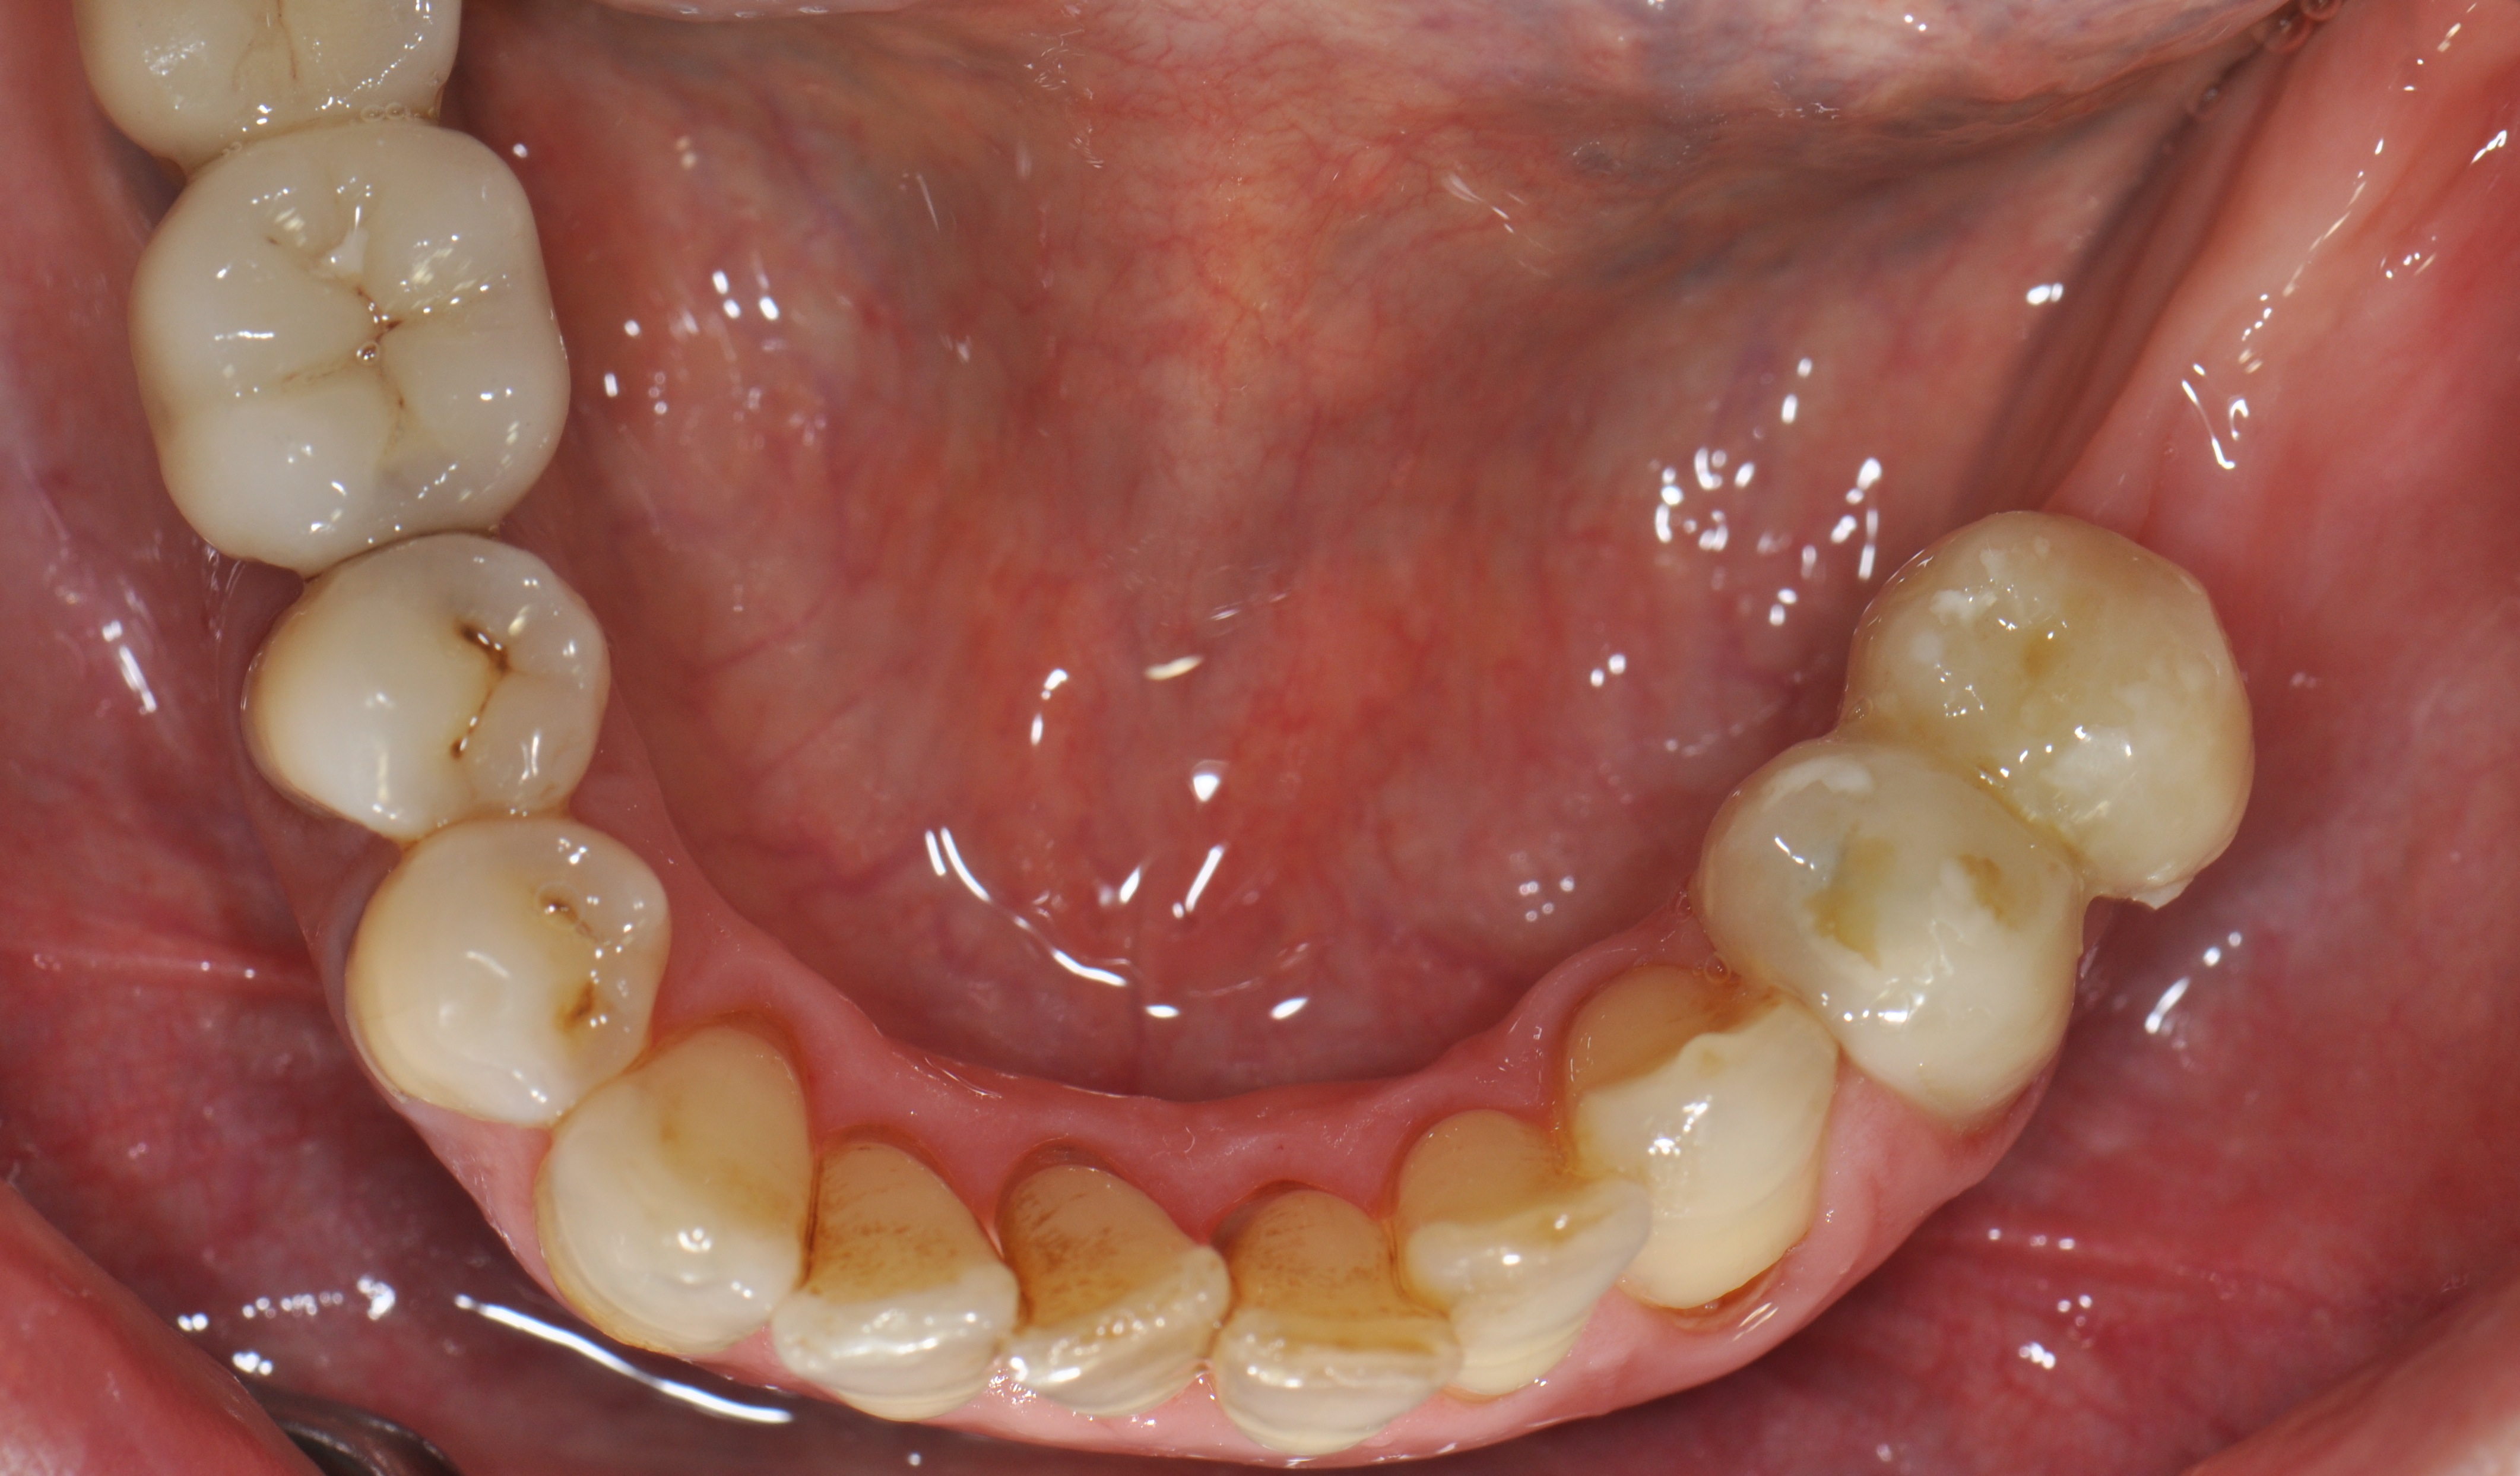

A 52-year-old patient is a referral and has been wearing an immediate provisional partial denture after replacement of her worn and fractured fixed partial denture. As a definitive treatment solution, the patient desired "beautiful and long-lasting" implant-supported single crowns. Clinically the CT-scan revealed a very narrow bone crest ("knife-edge") in the 3rd quadrant. Implant placement has been planned with a simultaneous GBR procedure.